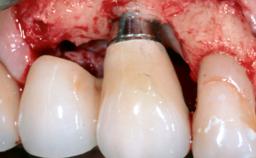

Mauricio Araujo and Flauvia Matarazzo present this straightforward clinical case, demonstrating the potential effect of implant placement depth on the resolution of peri-implant treatment. A 42-year-old systemically healthy female patient, a non-smoker with no history of periodontitis, was treated at the Dental Clinic at the State University of Maringá, Brazil between 2008 and 2009, when she received five implants restored with single crowns at sites 14, 26, 27, 36, and 46. After delivery of the implant-supported prosthetic restorations, the patient was enrolled in the supportive peri-implant therapy (SPiT) maintenance program at the same university.